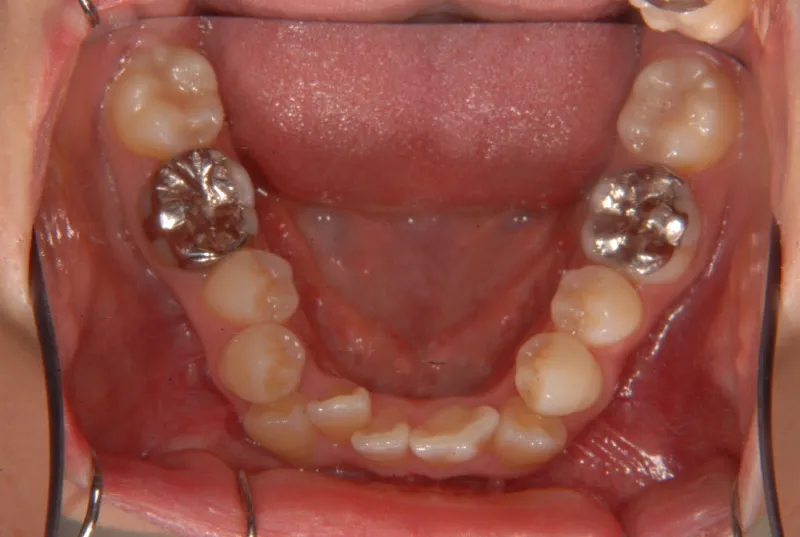

上下ガタガタで、下の歯は癒合歯(2本がくっついて1本の歯)です。

治療前と治療後で下の歯の銀歯がなくなっています。

これは銀歯の第1大臼歯を抜いて第2大臼歯、第3大臼歯の親知らずを使いました。